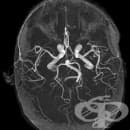

Функционален ЯМР на мозък

Функционален ЯМР на мозък - изображение

Функционалната магнитно-резонансна томография (fMRI) на мозъка е неинвазивно образно изследване, чрез което се проследява мозъчната дейност. Чрез fMRI (functional magnetic resonance imaging) се изследват множество мозъчни функции - говор, памет, моторна дейност, сетивност, зрение и други.

Функционалният магнитен резонанс на мозъка е базиран на същата технология, използвана и при стандартния ядрено-магнитен резонанс (MRI) - неинвазивен тест, който използва силно магнитно поле и радиовълни за създаване на детайлни изображения на структурата на мозъка. Докато при стандартната магнитно-резонансна томография се търсят промени в структурата на мозъка, при fMRI чрез проследяване притока на кръв в мозъка се отчита мозъчната активност.

Този метод се основава на изобразяването на концентрацията на оксихемоглобин, поради увеличено използване на килород в активираните чрез различни тестове мозъчни зони. Пациентът ще бъде помолен да извършва малки задачи, като например отговаряне на лесни въпроси, наблюдаване на различни изображения или извършване на елементрни движения с пръстите.

С помощта на функционалния ЯМР на мозък се получава информация за локализацията и латерализацията на мозъчните функции.

Чрез метода могат да се изследват речевите центрове в мозъка (центъра на Брока и зоната на Вернике), сензомоторната зона в мозъчната кора и други зони в мозъка свързани с определени фукции.